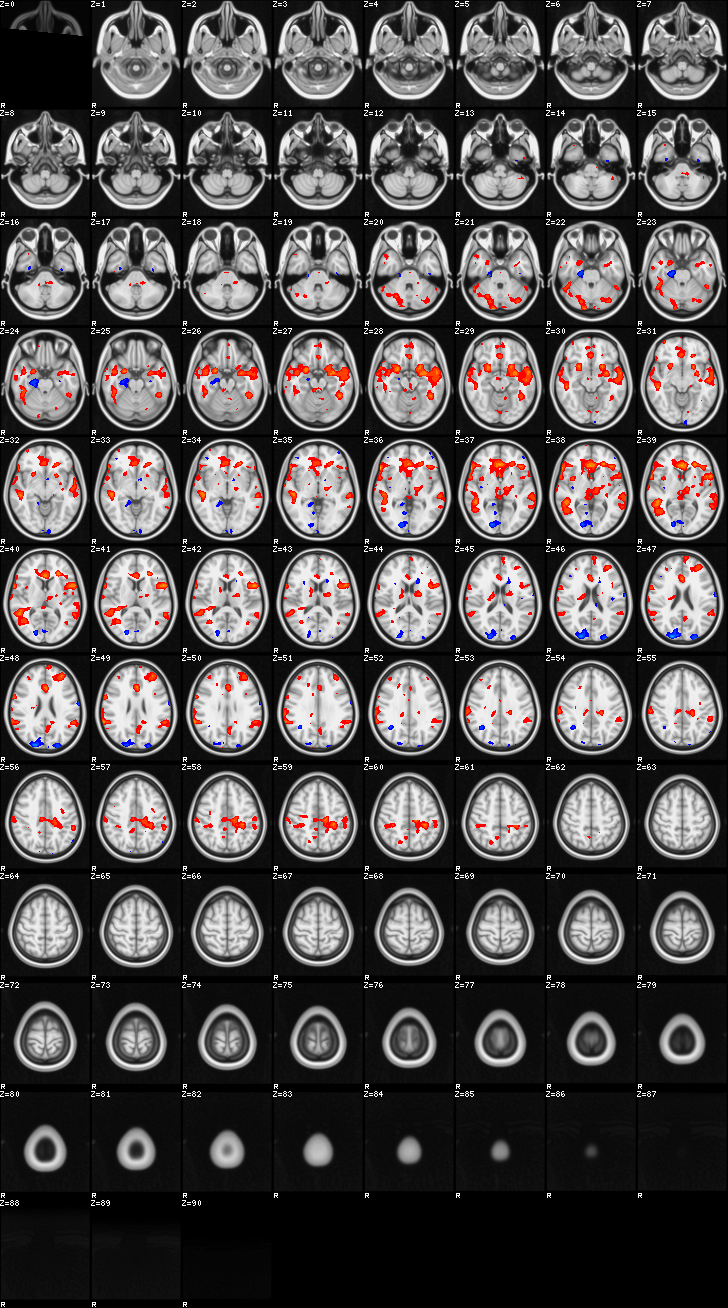

Fixed Effect¶

ATM it is 8 subjects, 8 mm FWHM spatial smoothing, preliminary results only

Images thresholded abs value > 2.3 and colormap goes from 2.3 to 5 (red->yellow) or -2.3 to -5 (blue->lightblue)

Contrasts:

- FgtC

- Familiar > Control

- FltC

- Well – the opposite, and since both sides are plotted, it is just inverted colormap

00-FgtC¶